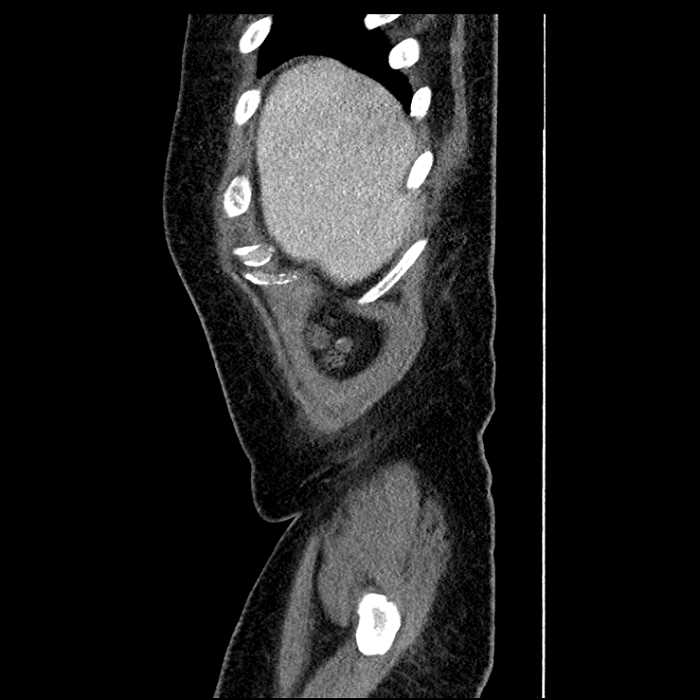

Age: 63

Sex: Male

Indication: Abdominal pain

• Large fluid density structure in hepatic segments 7 and 8 measuring 10 x 7 x 7 cm with internal septation and circumferential ill-defined low density compatible with edema

• Peripherally enhancing subcapsular collections along the anterior margin of the left hepatic lobe measuring 3 x 1 cm and 2 x 1 cm

• Hepatic abscess

Acute sigmoid diverticulitis complicated by a small contained perforation and a large abscess in the right hepatic lobe. Additional small subcapsular abscesses along the anterior margin of the left hepatic lobe.

• The classic CT imaging appearance is a double target sign with internal low density surrounded by an internal enhancing rim (capsule) and a low density external rim (edema)

Hepatic abscess showing the double target sign with low density internally surrounded by a thin inner enhancing rim (red arrow) and ill-defined outer low density rim (yellow arrow). Blue arrow indicates an internal septation. Red arrows: additional smaller subcapsular abscesses. Red arrow: focal contained perforation associated with diverticulitis.